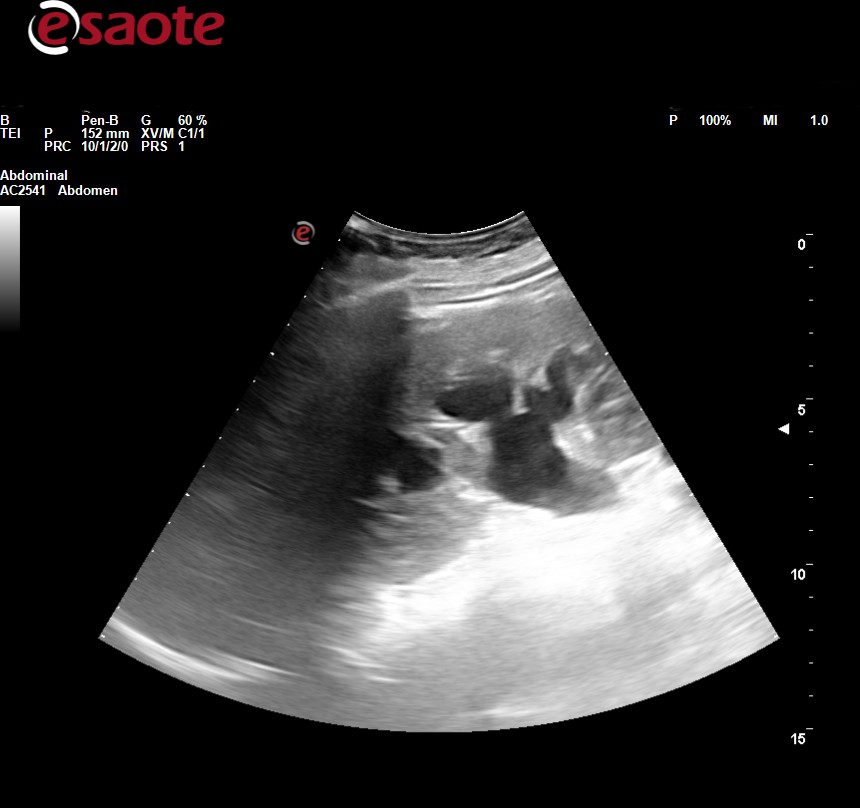

Ecografía clínica abdominal: observamos dilatación ureteropielocalicial bilateral junto con pared engrosada de la vejiga.

JC: hidronefrosis bilateral con engrosamiento de la pared vesical.

Se la deriva a urgencias hospitalarias, donde amplían estudio con analítica general (HB 9.1) bioquímica (creatinina 4.2, FG 11), urocultivo (negativo), p. de coagulación (normal), ecografía( obstrucción de vía urinaria bilateral asociada a engrosamiento mural vesical con signos de vejiga de lucha no se puede descartar malignidad), TAC abdominopélvico (riñón izdo atrófico, dilatación de la vía urinaria con aumento marcado y difuso de las paredes de la vejiga y formaciones diverticulares en ambas caras laterales), cistoscopia (vejiga de aspecto inflamatorio, engrosada, parcheada), biopsia (inflamación crónica) y pielografía descendente (permeabilidad de ambos uréteres con adecuado paso de contraste a vejiga)